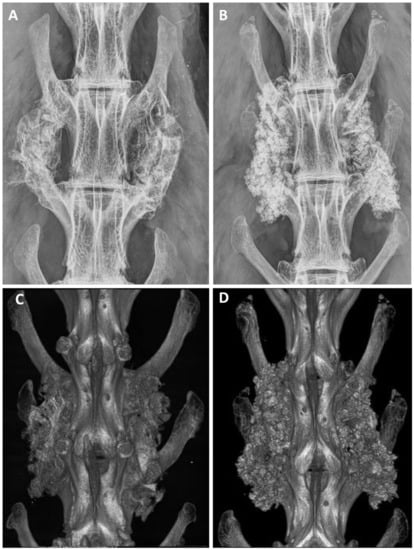

After euthanasia, anteroposterior radiographs were analyzed to evaluate the implantation. The analysis by radiography and micro-CT revealed successful implantation in all animals, and no adverse bony reactions or graft migration (Figure 4). The grading distribution according to the Lenke scale was comparable between ABG and BCP-EP/ABG with no statistical difference. A high occurrence of Grade A was observed at 12 weeks for both groups through radiographic analysis and micro-CT scans, indicating the presence of a solid bilateral fusion at this timepoint. The fusion rates were 62.5% and 75% for BCP-EP/ABG and ABG, respectively, according to both radiographic and micro-CT analysis.

Figure 4.

Representative examples of Faxitron radiographs taken after 12 weeks for (A) ABG and (B) BCP-EP/ABG. Representative examples of 3D micro-CT reconstructions taken after 12 weeks for (C) ABG and (D) BCP-EP/ABG. The Faxitron radiographs and micro-CT reconstructions show the presence of graft material bridging the intertransverse process space of the treated levels in all groups.